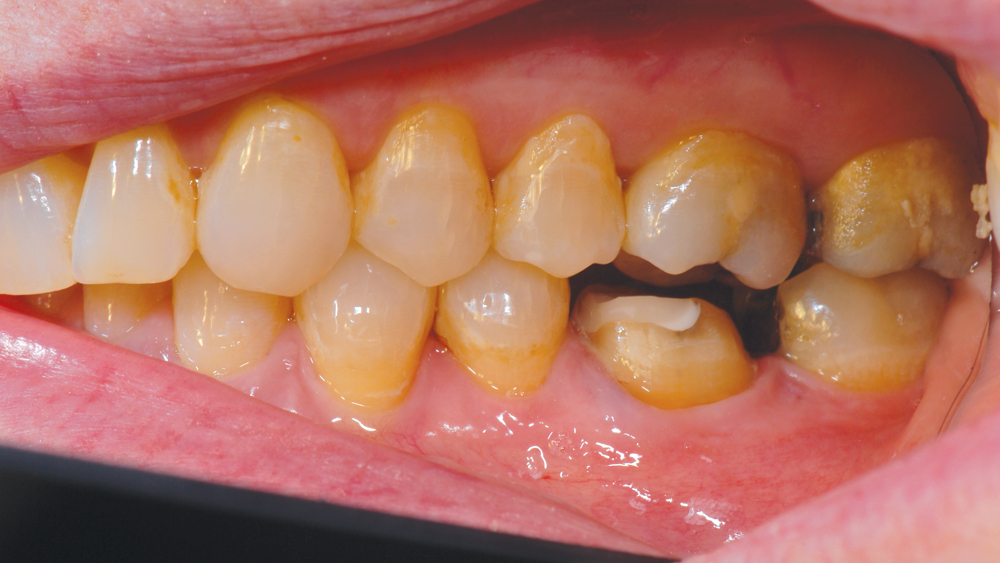

CASE REPORT

The following case highlights the efficient, user-friendly scanning capabilities of the iTero Element scanner, as well as the clinical advantages of connecting to the glidewell.io In-Office Solution for single-appointment dental restorations. The patient sought treatment for a damaged mandibular first molar with a cusp fracture. Because the case called for a single crown and high-strength zirconia, the patient was an ideal candidate for a same-visit restoration milled from a BruxZir NOW milling block. After preparing the tooth and taking an intraoral scan, the crown was fabricated within 40 minutes using the fastmill.io In-Office Unit. The final restoration fit perfectly without adjustment and exceeded the expectations of the patient, who was thrilled that she didn’t have to schedule a second appointment for the crown delivery.